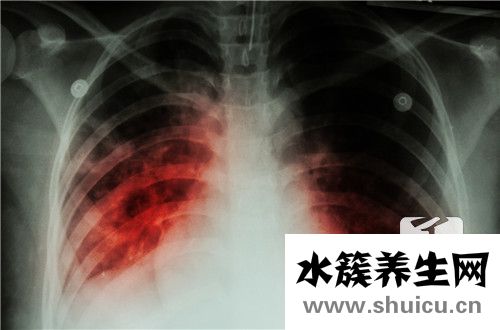

我堅信,每個人都會在一些時代的影視作品中看到一個場景,那就是肺結(jié)核患者因為得不到很好的治療而死于仇恨。事實上,現(xiàn)代社會的人對肺結(jié)核等疾病沒有很好的了解。如果換個名字,就知道是什么病了。其實...